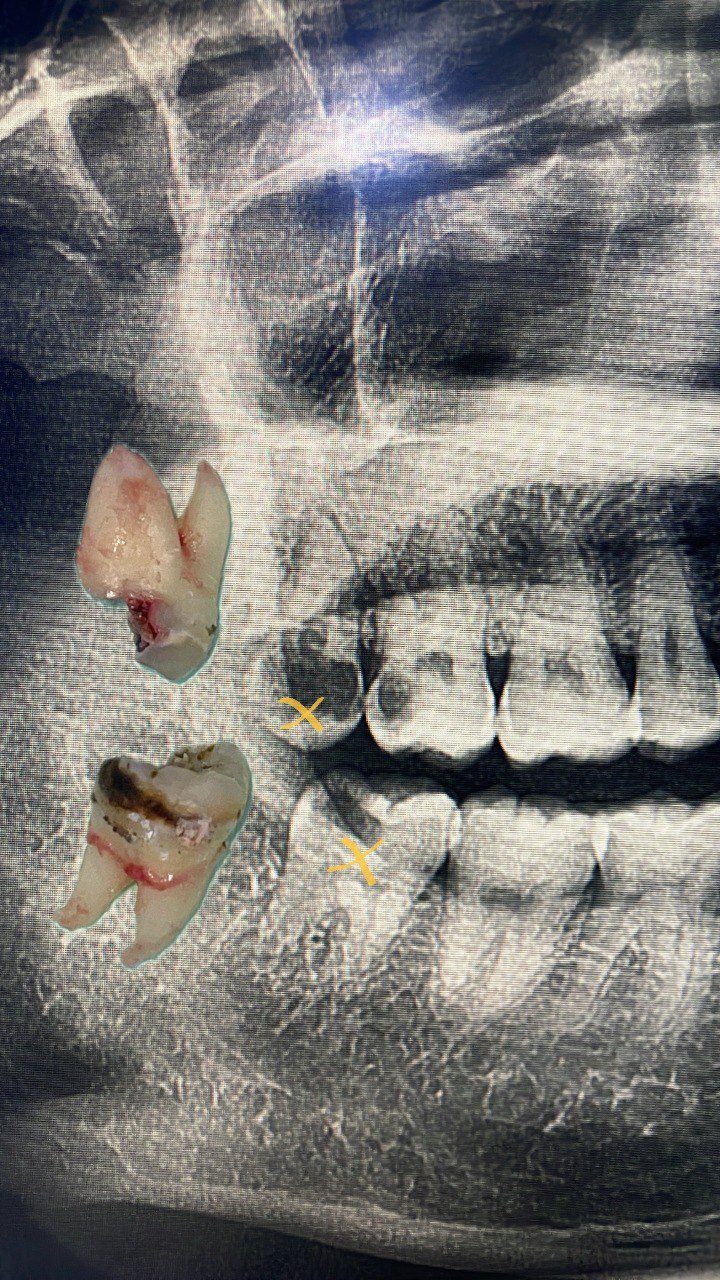

Minor Oral Surgery (MOS) is a routine dental procedure used to treat conditions such as impacted wisdom teeth, broken tooth roots, or oral infections that require more than standard dental care.

At Lau Dental Clinic & Surgery, we are fully equipped with on-site X-ray facilities, allowing us to assess and diagnose your condition quickly and accurately — often enabling same-day treatment. With extensive experience in managing a wide range of MOS cases, our highly skilled dental surgeon can perform most procedures safely and efficiently during your visit.

Minor Oral Surgery involves small surgical procedures done inside the mouth, often under local anaesthesia. The most common reason patients need MOS is to remove impacted or partially erupted wisdom teeth. However, it’s also used for removing broken tooth roots, treating dental cysts, or even preparing the mouth for dentures or implants. Unlike major surgery, MOS is minimally invasive, doesn’t require general anaesthesia, and is usually completed in under two hours.

At Lau Dental Clinic & Surgery, the process begins with a thorough consultation and digital X-ray, all done in-house. This allows us to assess your condition on the spot — and in many cases, proceed with treatment on the same day.

Once you're comfortable and the area is numb, our experienced dentist gently makes a small incision to access the tooth or problem area. Depending on the complexity, the tooth may be removed whole or in smaller sections. The site is then cleaned and stitched if necessary. Most MOS procedures here take only about 1 to 1.5 hours, and patients are often surprised by how quick and painless it feels.